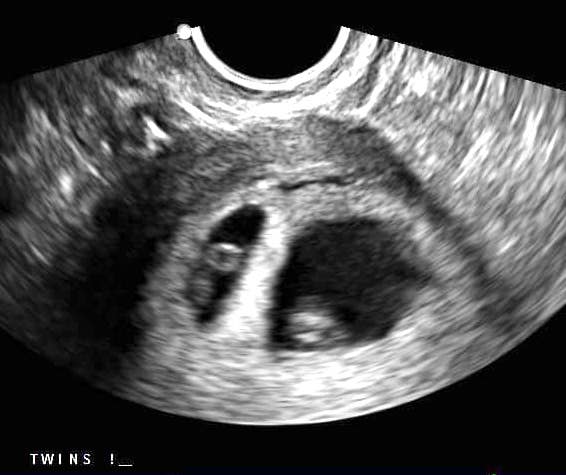

Early Twin Ultrasound at 7 Weeks

The earliest your doctor would likely order an ultrasound confirming twins would be 4 weeks pregnant. But unless you are going through fertility treatments, doing an ultrasound before 6 weeks isn’t very common, with the exception of complications. Women who are going through fertility treatments or have early complications may be able to have an early twin ultrasound at 4 or 5 weeks pregnant and find out they are pregnant with twins.

At four to five weeks after a pregnant woman’s last period the ultrasound commonly shows a small collection of fluid within the lining of the uterus that represents the early development of the gestational sac. At about five and a half weeks after a pregnant woman’s last period the ultrasound typically shows a gestational sac and within it we can see a 3-5 mm bubble-like structure, which is the yolk sac. At approximately six weeks after a pregnant woman’s last period, we can see a small fetal pole, one of the first stages of growth for an embryo, which develops alongside the yolk sac.

Can You Tell at 7 Weeks if Its Twins?

Yes! You’d need to have an ultrasound at 7 weeks to confirm a twin pregnancy. Your twin belly at 7 weeks may not look like much of a belly at all, so getting in to your doctor for an ultrasound is key to find out if you’re really having twins.